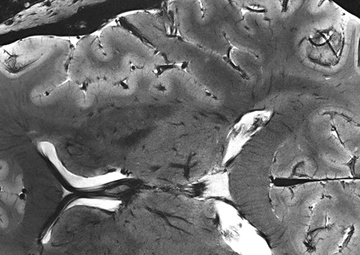

A brain scan from a 7T MRI scanner at the Athinoula A. Martinos Center for Biomedical Imaging at Massachusetts General Hospital shows microscopic detail that would be unobservable with conventional scanners. Defense Logistics Agency Energy Aerospace Energy provided Harvard Medical School with the liquid helium needed to power the scanner. Photo courtesy of Athinoula A. Martinos Center....